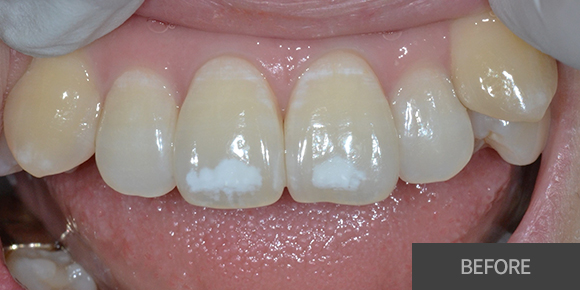

심미치료

심미레진

전체미백

실활치미백